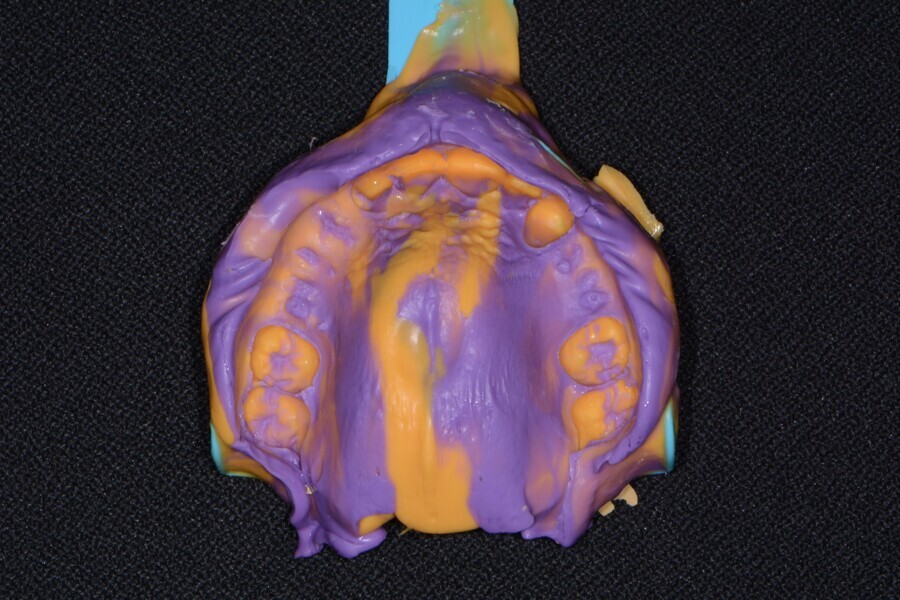

Fig. 7: Maxillary impression (Kettenbach).